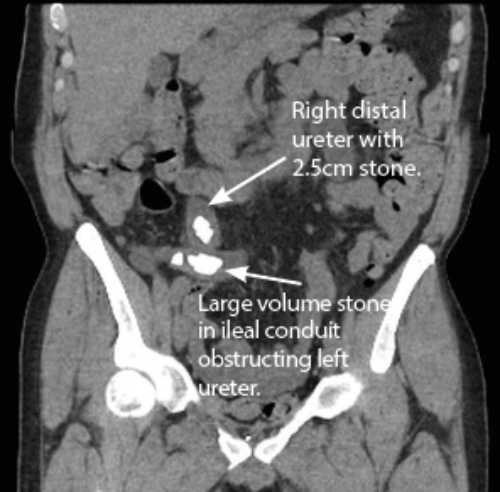

A systemically well 50-year-old male who had a cystoprostatectomy and ileal conduit formation for severe urethral 17 years prior presented with recurrent E coli urinary tract infections and acute kidney injury. A CT revealed severe bilateral hydronephrosis and hydroureter with two large distal right ureteric stones (total length 2.5cm, HU 1000 units) and multiple stones (largest 12mm with combined length of 4.5cm, HU 600) in his conduit which were obstructing his left ureter (Figure 2.). A recent MAG 3 scan revealed equal split function with sluggish drainage but no obstruction.

Bilateral nephrostomy tubes were placed and the renal function improved. Antegrade stents were placed but the right stent dislodged into the conduit requiring removal under fluoroscopy and the left stent failed to drain.